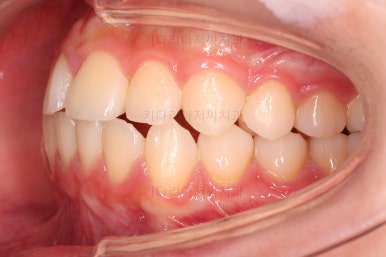

초진 시 다른 부위들 사진입니다.

약간의 주걱턱 느낌에 약간의 돌출감, 전반적인 치열의 가지런한 느낌은 나쁘지 않았지만 약간의 불량한 교합상태였어요.

다른 부분은 크게 바꾸지 말고 약간의 교합조절과 어금니 치료에 초점을 맞춰서 교정치료 계획을 잡았습니다.

전후사진을 비교해볼게요.

약간의 주걱턱, 돌출입은 고칠 의사가 없어서 그대로 유지하였고 주걱턱 패턴으로 인한 부정교합 부분을 개선했으며 무엇보다 중요한 것은 쓰러져서 많이 썩어있던 치아를 자칫 치료 못할 뻔 했는데 교정치료와 병행하여 훌륭하게 치료하여 살려 썼다는 점이었어요.